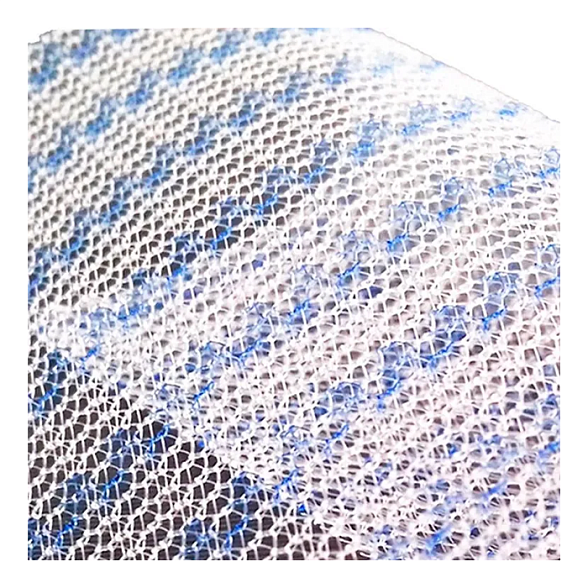

Эндопротез-сетка (сетка хирургическая) полипропиленовый для восстановительной хирургии ЭСФИЛ лёгкий, 20х15 см, Линтекс

Эндопротез-сетка полипропиленовая ЭСФИЛ лёгкий для восстановительной хирургии

Представляем вашему вниманию высокотехнологичный хирургический имплант — эндопротез-сетку полипропиленовую ЭСФИЛ лёгкий от ведущего российского производителя «Линтекс». Это современное решение для пластики и укрепления мягких тканей, разработанное с учетом потребностей как хирурга, так и пациента. Изделие размером 20х15 см является универсальным инструментом в арсенале специалистов, выполняющих сложные восстановительные операции.

- Оптимальная интеграция с тканями: Особое плетение и структура материала способствуют активному прорастанию соединительной ткани (фиброзной и коллагеновой), обеспечивая надежную фиксацию импланта и формирование единого анатомического комплекса.

- Лёгкость и эластичность: «Лёгкая» модификация сетки обладает сниженной плотностью и массой, что минимизирует ощущение инородного тела у пациента после операции и повышает комфорт в отдаленном периоде.

| Структура | Макропористая, неабсорбируемая (нерассасывающаяся) |